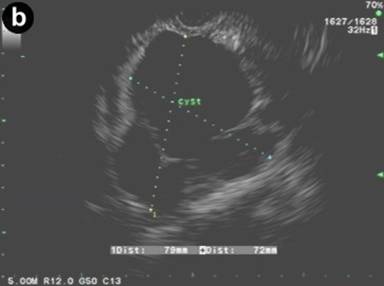

Figure 1. a. Contrast enhanced abdominal CT scan showing a cystic lesion adjacent to the head of the pancreas and anterior to the right kidney from Case #1. b. Linear EUS image showing the anechoic cyst with several thin septae from the same patient. |

Curved linear-array EUS (GF-UCT140, Olympus America Co., Center Valley, PA, USA) was performed and a large 9x8 cm anechoic cyst was noted adjacent to the caudate lobe of the liver and the head of the pancreas. There were several thin septations within the cyst but no associated solid masses or mural nodules were seen. The imaged portions of the liver, pancreas, and biliary tree were otherwise normal. The largest loculation closest to the transducer was aspirated using a 19 gauge EUS-FNA needle (Echotip® Ultra, Cook Medical Inc., Winston-Salem, NC, USA) and 200 mL of thick yellow-white, chylous appearing fluid was removed. The laboratory analysis of the cystic fluid revealed a carcinoembryonic antigen (CEA) level less than 0.5 ng/mL (reference range: 0-3 ng/mL), an amylase level of 70 U/L (reference range: 0-10 U/L), and a triglyceride level of 798 mg/dL (reference range: 0-10 mg/dL). Cytologic evaluation was negative for malignancy and showed only benign epithelial cells with a few scattered lymphocytes on the smear. A diagnosis of pancreatic cystic lymphangioma was made and no further diagnostic testing such as immunostaining was conducted. Patient was offered surgical referral for removal but declined and has subsequently been followed for 20 months. He remains asymptomatic and repeat CT scans have shown no change in the cyst.